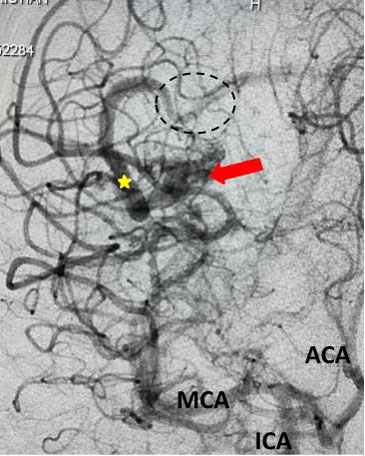

Fig 3. Lateral view, late-arterial phase of a right internal carotid artery (ICA) injection. Filling of the AMV (red arrow) by the fetal posterior cerebral artery (PCA) and small middle cerebral artery feeder (blue arrow). The large tortuous draining vein (yellow star) with venous stenosis and the suggestion of clot (dotted circle) can be seen.

The patient was taken to the angio-suite where an angiogram confirmed a high flow, high pressure AVM fed primarily by the posterior cerebral artery with a small collateral from the middle cerebral artery (Fig 2 and 3). The AVM drained into a tortuous, partially occluded and stenotic single draining vein.